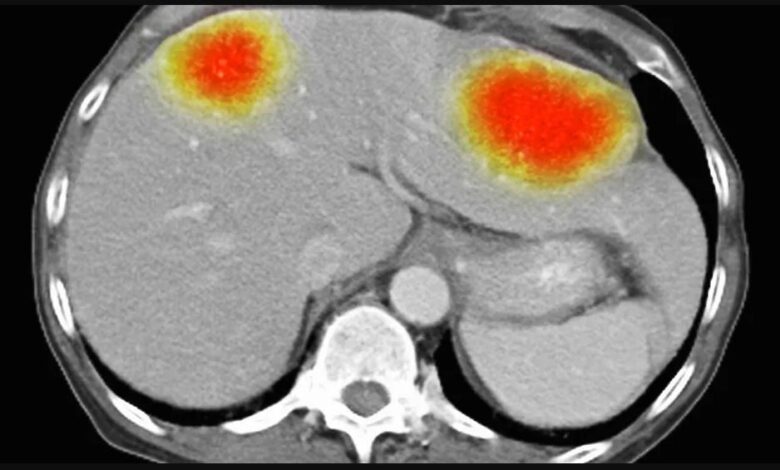

ويعد الورم الدبقي من أكثر أنواع السرطان عدوانية وصعوبة في العلاج. ويبلغ معدل البقاء على قيد الحياة لمدة خمس سنوات 6.8% فقط. ويقدر متوسط البقاء على قيد الحياة للمرضى بثمانية أشهر فقط بعد التشخيص. وتنتشر بعض الأنواع بشكل خاص عند الشباب.

ووجد فريق نوتنغهام أنه عند استهداف #خلايا_الورم_الأرومي الدبقي بتقنية bio-antenna، تُركت الخلايا السليمة المحيطة بالسرطان دون مساس.